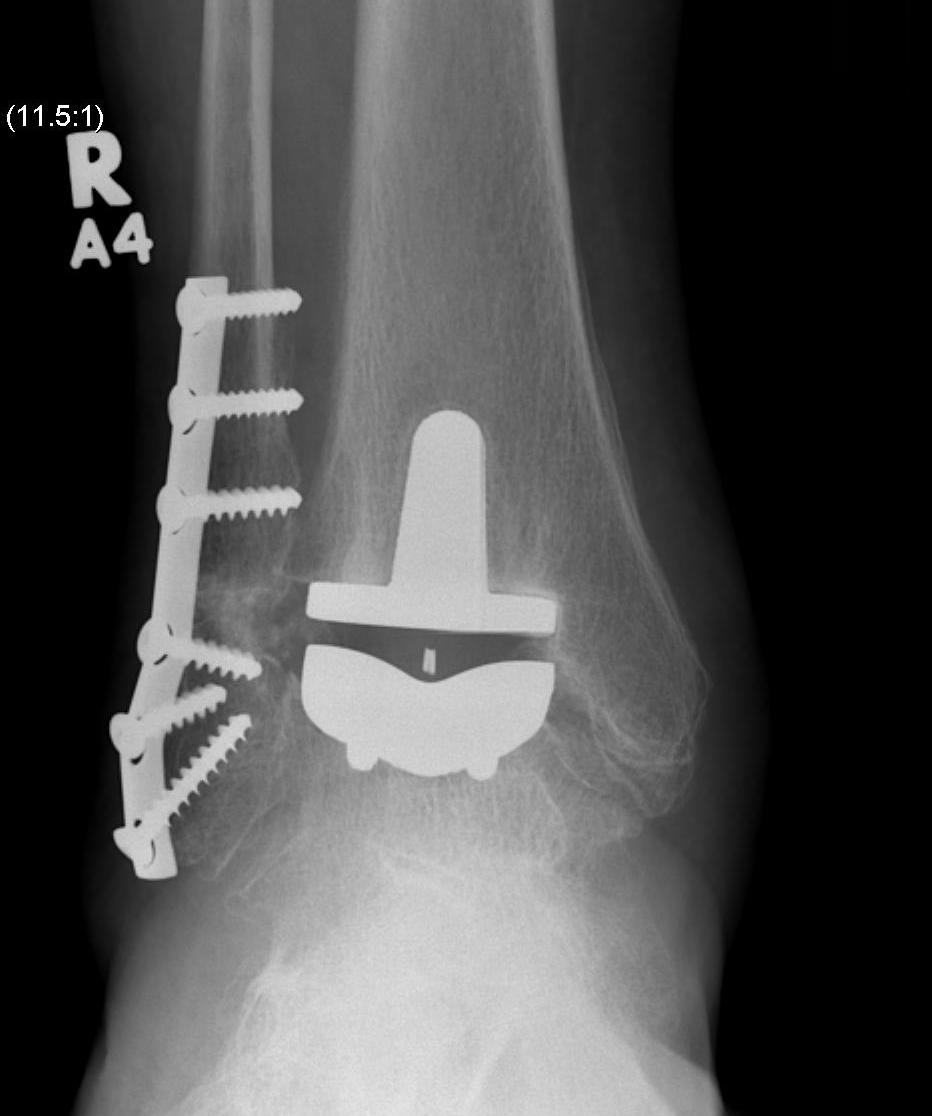

Ankle Arthroplasty

History

First generation (late 70s early 80s)

Results